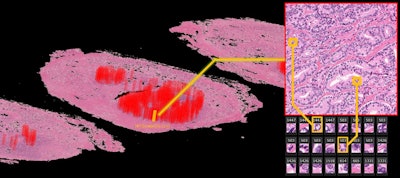

The team used images from 100 patients at NMSH to extract the features, while the rest of the NMSH dataset was used to validate their method. Lead researcher Dr. Yoichiro Yamamoto, PhD, and his colleagues trained two unsupervised deep neural networks, known as deep autoencoders, to reduce the 10-billion-scale pixel data into 100 features. They achieved this by using both low-resolution and high-resolution histopathology image patches, inspired by the diagnostic process of pathologists. The computation was performed on AIP's Riken Alp Deep Learning Environment (RAIDEN) supercomputer.

Finally, the authors evaluated the AI-generated features. They retrieved the most representative images for each of the features and asked an expert pathologist to examine them.

"In summary, the pathologist found that the deep neural networks appeared to have mastered the basic concept of the Gleason score fully automatically, generating explainable key features that could be understood by pathologists," they noted.